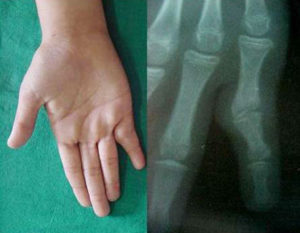

Характерный признак, по которому можно заподозрить развитие анкилоза – неподвижный деформированный сустав. Часто деформация развивается в неестественном положении, «невыгодном» для больного. При попытке движения в суставе наблюдается полная потеря функциональности.

Распознать патологию несложно. При осмотре пораженного сустава наблюдается изменение формы суставной сумки и полное отсутствие возможности движения. Из аппаратных методов назначают рентгенографию или компьютерную томографию, которая позволит детально рассмотреть дегенеративные изменения в суставе.